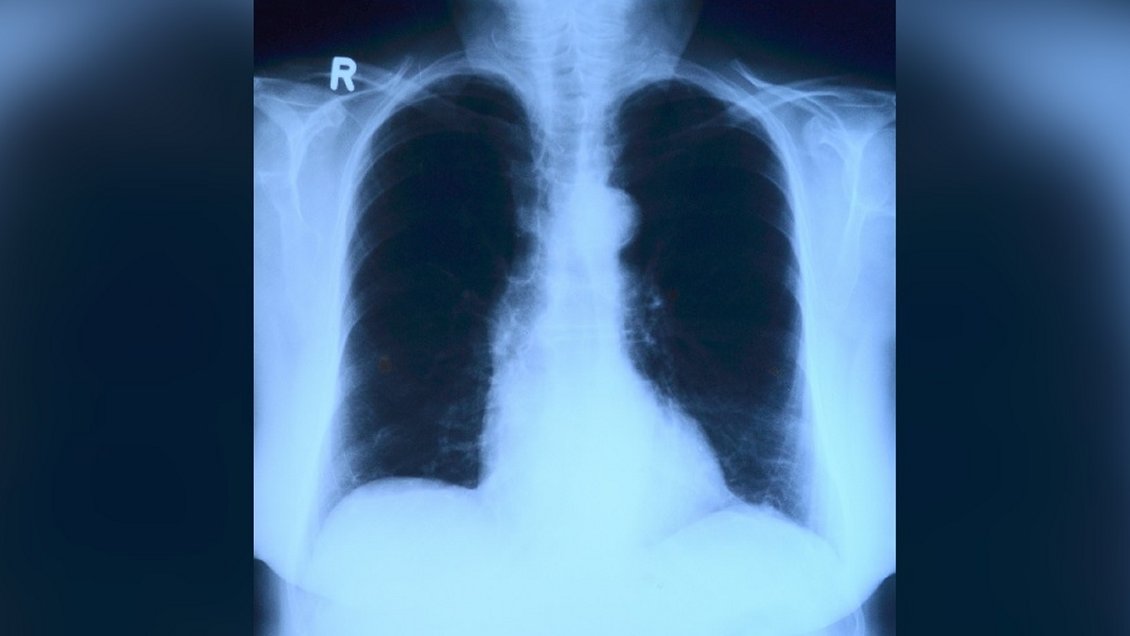

Imagen foto_00000001

Al procesar radiografías de tórax, el machine learning es capaz de detectar con alta precisión qué pacientes presentan Covid-19 y cuáles no.

Una investigación liderada por el Centro de Data Science de la Escuela de Ingeniería Industrial de la Pontificia Universidad Católica de Valparaíso demostró que el machine learning (herramienta de inteligencia artificial de aprendizaje automático) aplicado a radiografías de tórax es capaz de diagnosticar con certeza el Covid-19.

Según señala en sus conclusiones -que fueron publicadas en la revista científica Signa Vitae, perteneciente al ISI web of Science (ver archivo adjunto)- esta técnica es capaz de diferenciar entre pacientes con Covid-19, personas sanas y pacientes con neumonía con una alta precisión (hasta un 90 por ciento), a bajo costo, y con infraestructura computacional sencilla y básica, lo que podría impactar positivamente en sectores donde no existe acceso ni infraestructura para el diagnóstico con PCR.

Incluyó un experimento estadístico diseñado para verificar si herramientas de aprendizaje automático, como máquinas de soporte vectorial y bosques aleatorios, detectaban pacientes Covid-19 positivos entre diferentes imágenes de rayos X de pacientes sanos, con neumonía y con coronavirus. "¿El resultado? Hasta un 90 por ciento de sensibilidad y especificidad en el diagnóstico", destacó a PUCV.